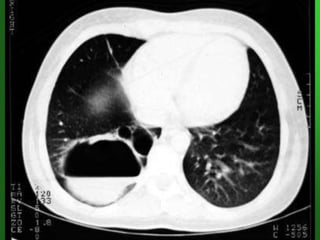

TB